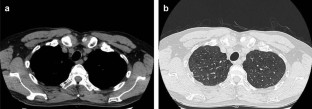

Fig. 2